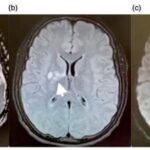

Se pueden mencionar al respecto los estudios que han encontrado en pacientes dependientes al alcohol una disminución del volumen de sustancia gris en el área de la corteza frontal, el hipocampo y el tálamo. El volumen de las sustancias blanca y gris también se puede ver disminuido en el área periventricular, la protuberancia y el cerebelo. Estos déficits de volumen también se han localizado en la corteza prefrontal dorsolateral derecha, ínsula anterior derecha, en el núcleo accumbens y en la amígdala izquierda(16) (ver Imagen 1).

Asimismo, como se indicó previamente, a través de la TC también se puede observar el deterioro de la microestructura cerebral por adicción al alcohol. El abuso de esta sustancia altera cinco fibras del cerebro, como el cuerpo calloso, el fondo de saco, la cápsula externa, el cíngulo circunvolución y el fascículo longitudinal superior, las que están involucradas en funciones como el procesamiento visoespacial y del lenguaje, la comunicación interhemisférica, la memoria, el procesamiento emocional, la toma de decisiones y la integración sensorial(16) (ver Imagen 2).